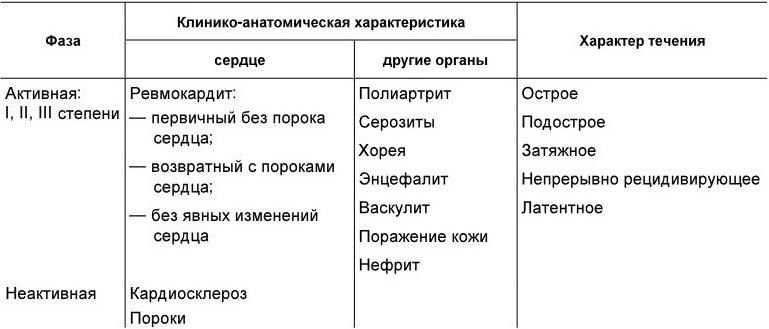

Классификация. В настоящее время нет общепринятой в мире классификации ревматизма. В нашей стране принята рабочая классификация ревматизма, в соответствии с которой выделяют активную и неактивную фазы ревматизма, оценивают остроту течения, наличие органных изменений и состояние кровообращения (табл. 1.14).

При остром течении ревматизма все клинико-биохимические изменения, свидетельствующие об активности процесса, ликвидируются в срок до 3 месяцев, при подостром – в течение 3 – 6 месяцев, при затяжном – в срок более 6 месяцев. Непрерывно рецидивирующее течение характеризуется постоянным обострением процесса, латентное – минимальными клинико-лабораторными проявлениями. Для активности III степени типичны яркие клинические проявления ревматизма в сочетании с выраженными лабораторными изменениями (нейтрофильный лейкоцитоз, СОЭ > 40 мм в час, резкое увеличение содержания фибриногена, С-реактивного белка, α2-глобулинов в крови, высокие титры антител к антигенам стрептококка). При активности II степени отмечается меньшая выраженность клинико-лабораторных изменений, а при I степени активности – минимальные изменения.

Таблица 1.14

Рабочая классификация ревматизма